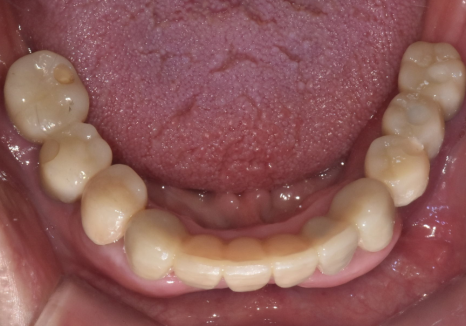

다행히 남길 수 있는 앞니들은

마모가 심하긴 했지만 뿌리는 괜찮았기에

신경치료 후 총 6개의 치아를 연결하는

브릿지 치료를 계획했습니다.

하악: 임플란트 5개 식립

아래 앞니 브릿지 및 어금니 크라운(#44)

다행히 뼈이식 부위도 잘 자리를 잡았고

임플란트도 아주 튼튼하게 고정된 것을 확인 후

보철을 올려드렸습니다.